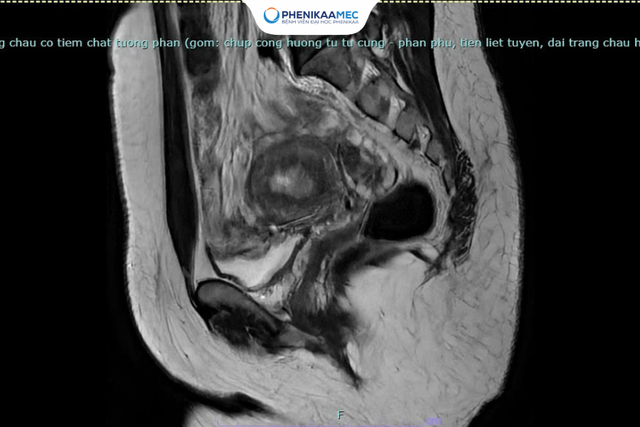

Đến với Khoa Phụ PhenikaaMec, người bệnh N.T.H.G được thăm khám lâm sàng kỹ lưỡng và thực hiện các đánh giá cận lâm sàng chuyên sâu. Kết quả chụp cộng hưởng từ vùng chậu có tiêm thuốc cản quang cho thấy hình ảnh dày niêm mạc tử cung kèm ngấm thuốc không đều, nghi ngờ tổn thương ác tính giai đoạn sớm. Chị H.G được chỉ định phẫu thuật cắt tử cung hoàn toàn và 2 vòi tử cung, vét hạch chậu và treo buồng trứng.

Hình ảnh MRI vùng chậu cho thấy niêm mạc tử cung dày, ngấm thuốc cản quang không đồng nhất, kèm tổn thương vùng chuyển tiếp gợi ý ung thư nội mạc tử cung giai đoạn sớm (FIGO IA)